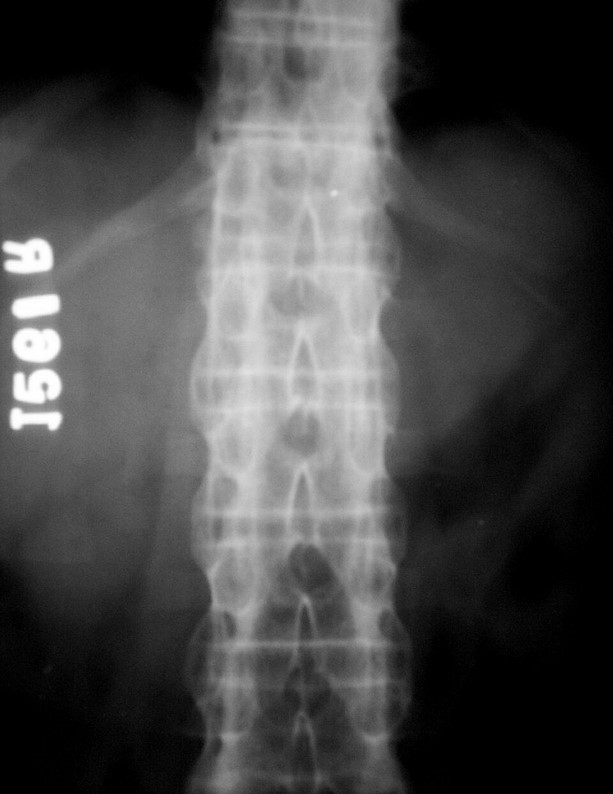

A S Bamboo spine 3

Magnified view – L S Spine